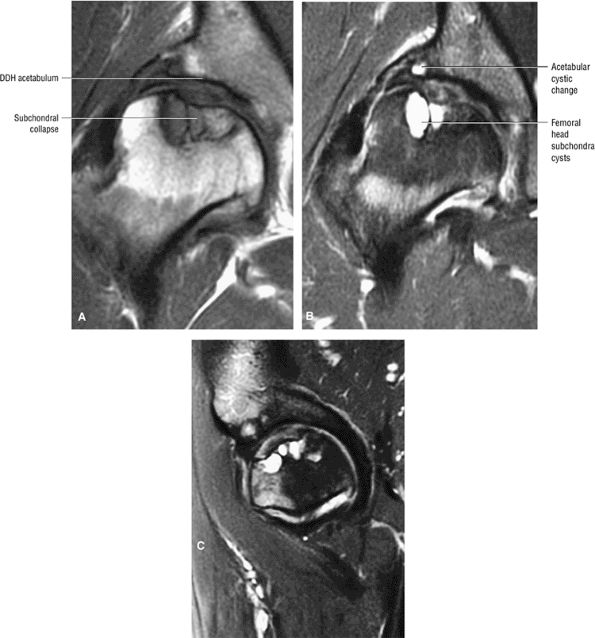

FIGURE 3.84 ● Osteonecrosis in a dysplastic hip with a shallow acetabulum. There is frank subchondral collapse and femoral head cystic change. Changes in the acetabulum represent superimposed degenerative arthritis with joint space narrowing. (A) T1-weighted coronal image. (B) FS PD FSE coronal image. (C) FS PD FSE sagittal image.

FIGURE 3.85 ● Coronal T1 FSE (A) and FS PD FSE (B) images showing AVN with associated synovitis. The central AVN focus demonstrates marrow fat signal intensity. Synovitis demonstrates intermediate signal intensity.

FIGURE 3.86 ● AVN associated with acetabular degenerative changes. Note the hypointense sclerotic reaction of the femoral head. (A) Coronal T1-weighted image. (B) Coronal FS PD FSE image.